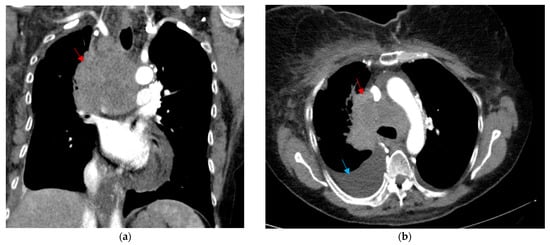

2. Case Description